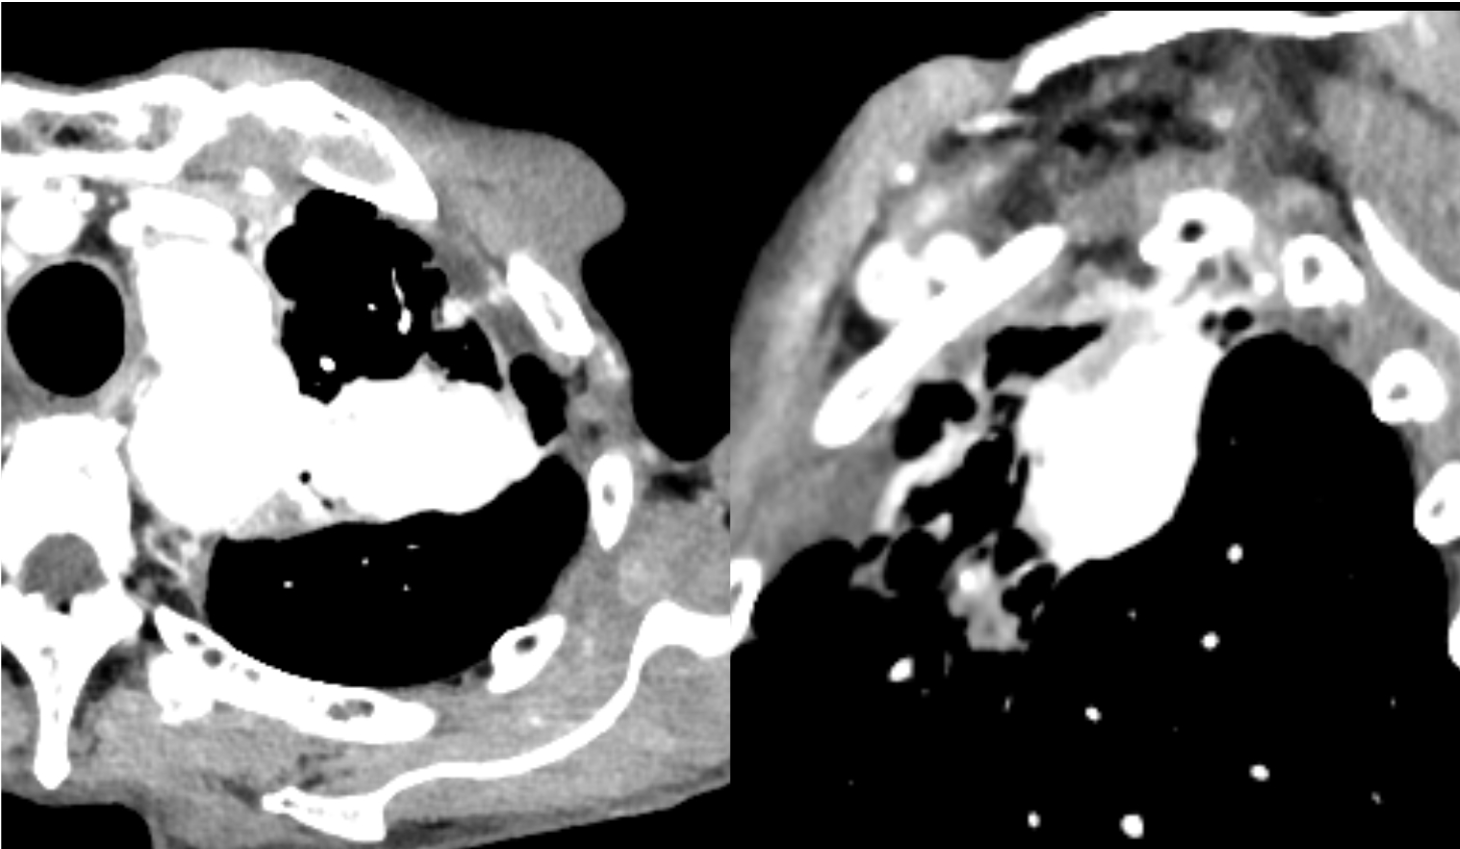

図2.造影CT早期相

早期相では腫瘤の造影効果は不明瞭である。

図3.造影CT後期相(Virtual Monoenergetic Image 40keV表示)

40keV表示では、腫瘤の造影効果が図4に比して強調されている。

図4.造影CT後期相(Virtual Monoenergetic Image 70keV表示)

70keV表示は、一般的な後期相の造影効果を表している。

図5.造影CT後期相(Virtual Monoenergetic Image 100keV表示)

100keV表示では、造影効果は減弱しているが、ノイズは軽減している。

図6.keVと腫瘤のROI値の関係を示したグラフ

keVを下げるほど、腫瘤の吸収値は大きく上昇する。